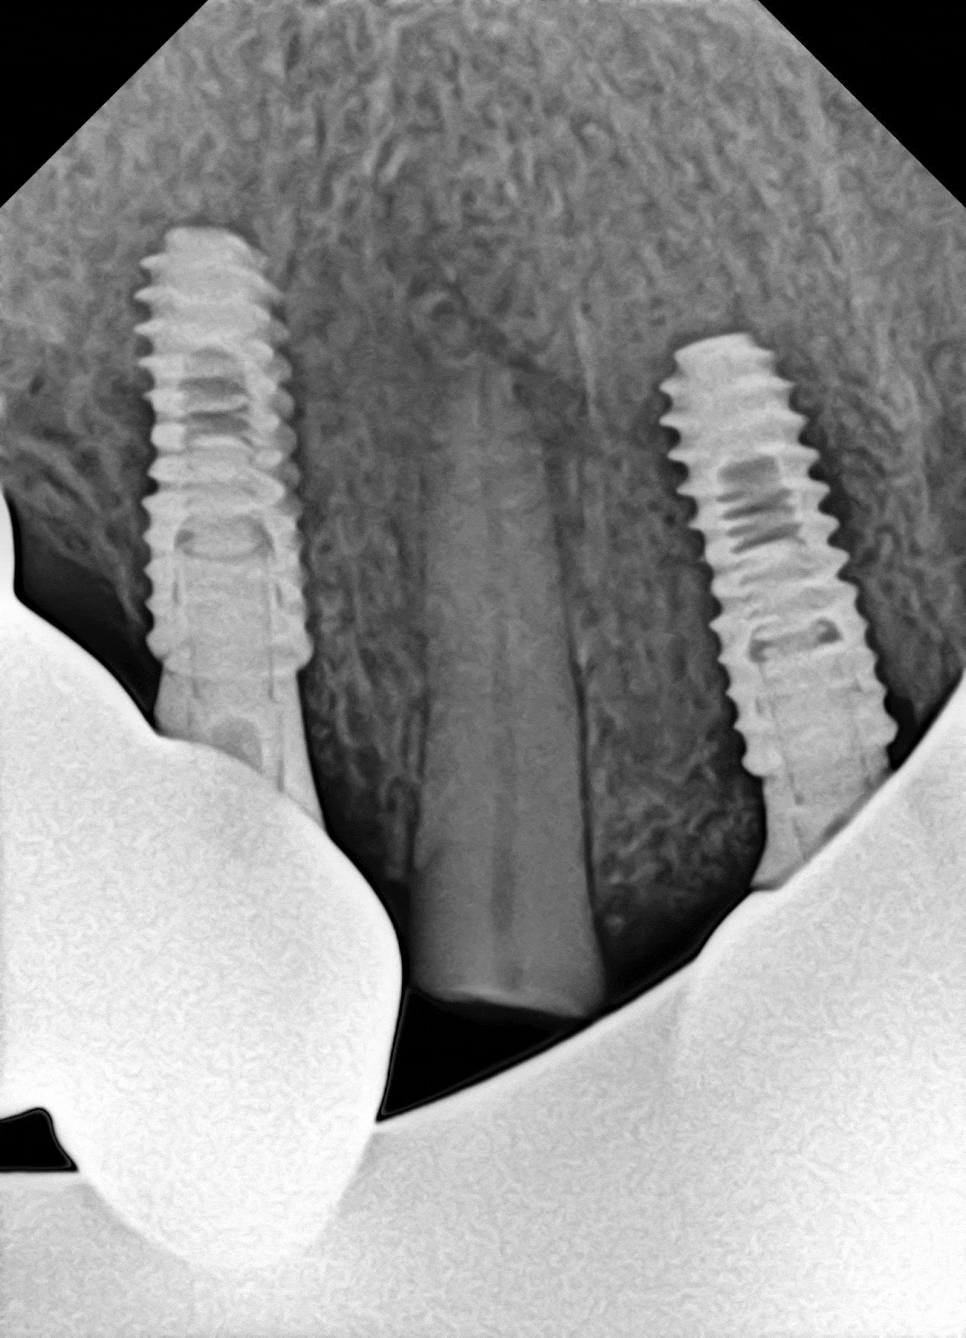

그래서 Panorama나 CBCT 같은 자료를 통해

내부 상태를 확인하게 됩니다.

당산동 치과 에서 준비한 사진을 보시면

안쪽 신경이 외부로 드러난 것을 확인할 수 있습니다.

파절 범위가 넓어 치수까지 침범했는데,

아직까지 염증 반응은 없었습니다.